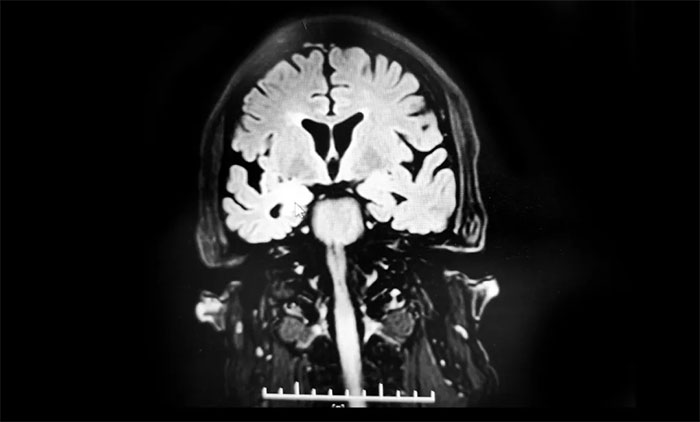

结合患者症状、病史,张静波主任考虑并不是单纯癫痫发作那么简单。头颅核磁平扫、增强没有发现问题,但是海马核磁检查发现异常:双侧海马萎缩,右侧为著伴右侧海马信号增高,需要考虑炎症、免疫、肿瘤等多种可能。

▲ 海马核磁检查发现异常:双侧海马萎缩,右侧为著伴右侧海马信号增高